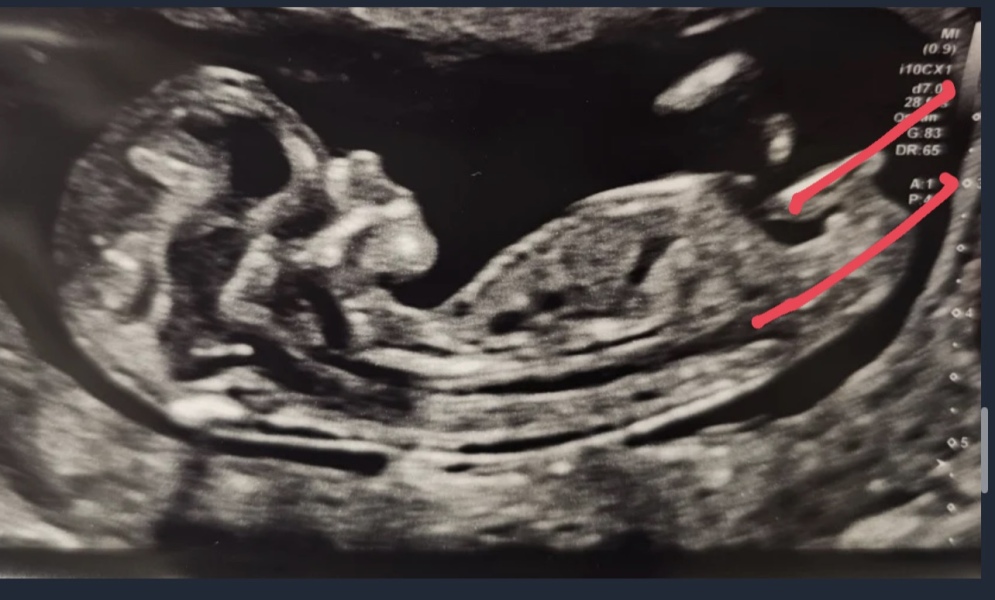

HolyMoly24 · 15/03/2024 11:04

There's officially a baby in there! All looking good and due date moved forward by one day. We walked out of the hospital after the scan and there was a huge rainbow too which felt a bit magical!

Can't wait to tell our DD tonight and then rest of family.

If anyone wants to guess based on the nub (what even is a nub?) then please feel free 😁

Good luck to everyone else having their scans today, I know there's a few of us x